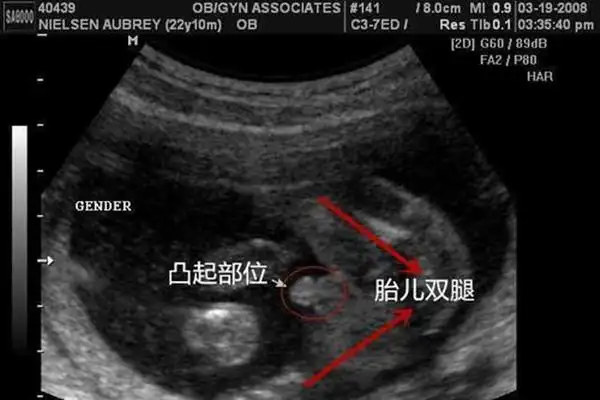

b超看男女b超单子看男孩女孩诀窍

四维彩超这些细节透露了胎儿性别这篇文章在各个宝妈群里疯传

胎儿性别是什么时候形成的生男生女谁的决定权大